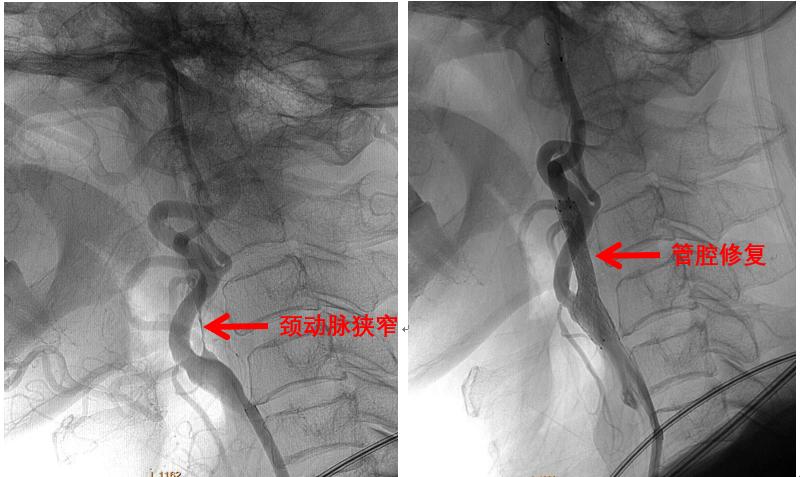

神经血管篇——颈内动脉狭窄

颈内动脉是向大脑供血的重要血管,单侧血管供血约占全脑血流量的40%~45%,这般举足轻重的血管一旦发生严重狭窄,什么灵光一现、思如泉涌、神机妙算您是铁定做不到了,丢三落四、老眼昏花估计难免,保不齐还要隔三岔五的到神经内科报到,而利用支架修复颈内动脉管腔的介入治疗兴起,可以从源头上减少脑梗塞的发生。

颈内动脉狭窄介入治疗